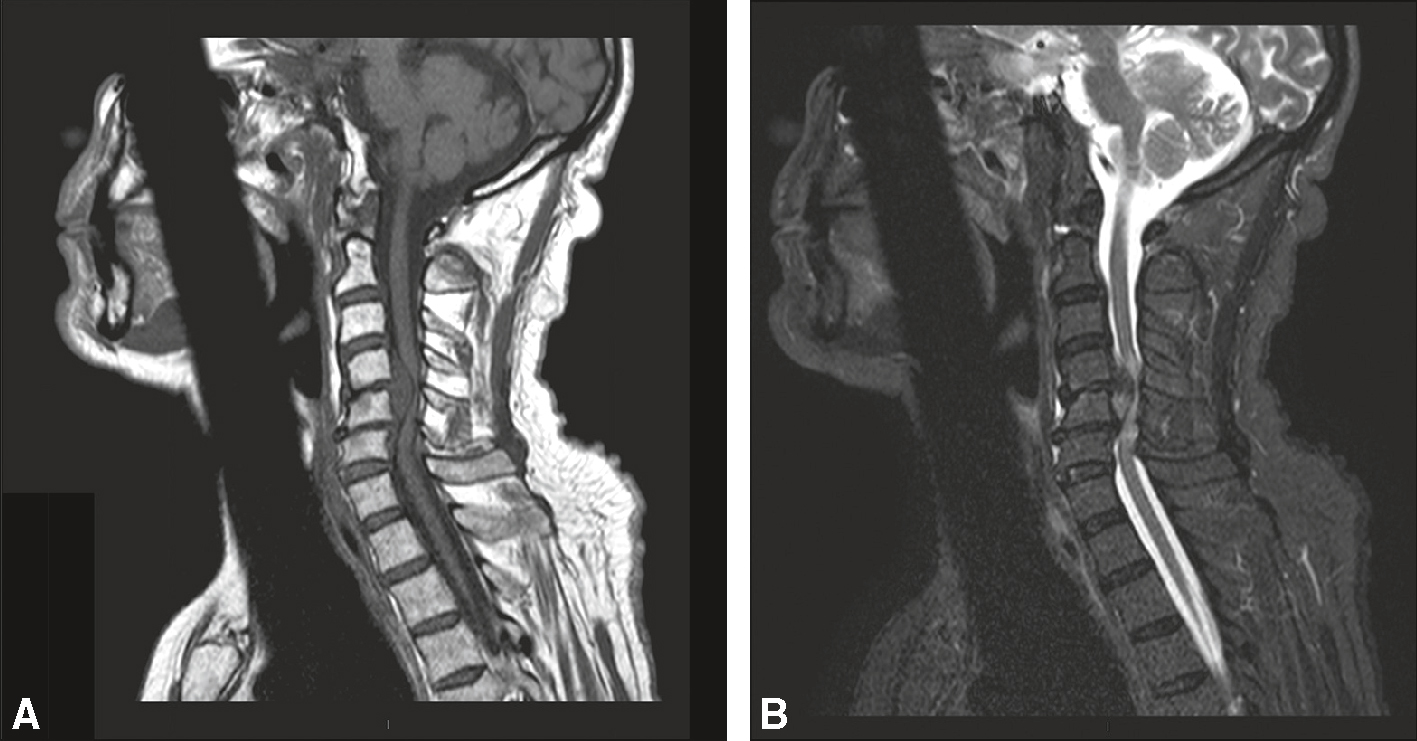

3 92Hernie discale

Préférentiellement au niveau cervical.

Elle peut être une étiologie de compression médullaire extradurale (fig. 7.5).

Compression médullaire due à une hernie discale exclue en C5-C6. Les espaces liquidiens périmédullaires sont laminés. Compression médullaire avec hypersignal intramédullaire en regard témoignant d’une souffrance, en absence d’anomalie osseuse associée. A. Sagittal T1. B. Sagittal T2.

Image en coupes sagittales d’une IRM cervicale, présentée en deux volets A et B, montrant une compression médullaire au niveau C5-C6. La vue A, en pondération T1, met en évidence les structures anatomiques avec un bon contraste entre la moelle épinière, les disques intervertébraux et les corps vertébraux. La hernie discale postérieure en C5-C6 apparaît comme une protrusion du disque comprimant visiblement la moelle. La vue B, en pondération T2, accentue la visibilité des liquides, soulignant un hypersignal intramédullaire à ce niveau, évocateur d’un œdème ou d’une souffrance médullaire secondaire à la compression. La hernie discale exclue, bien visible par la perte de continuité avec le disque d’origine, s’insinue vers le canal rachidien, réduisant significativement l’espace périmédullaire. L’ensemble suggère une atteinte compressive aiguë ou subaiguë nécessitant une prise en charge rapide pour éviter les séquelles neurologiques. L’alignement vertébral est conservé, et aucun signe de fracture ou lésion osseuse n’est observé dans les coupes visibles.